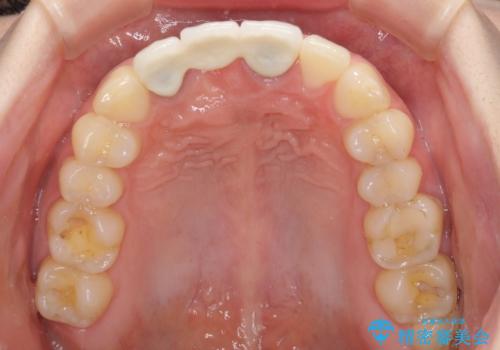

- 他院で装着したばかりの前歯のブリッジが気に入らず、作り替えを希望して来院された患者様です。

前院では、土台の金属を除去することは不可能であると言われたとのことでした。金属の土台が残っているとセラミックにグレーの金属色が透けて見えてしまうため、拡大鏡やマイクロスコープを用いて丁寧に除去し、天然歯の色に近いファイバーコアを植立することとしました。

また、歯とクラウンの境目が合っていない部分が多く、歯肉からの出血が認められました。